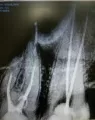

Здравствуйте, мне сняли старые коронки и подготовили зубы к протезированию, а протезист взял и обточил до дёсен зубы, которые шли под коронку, на мой вопрос зачем, он не дал ответа и нахамил. Не могли бы вы ответить, для чего он это сделал и как мне быть дальше, чтобы не усугубить ситуацию. Спасибо.

Добрый день. Все он правильно сделал, главное, чтобы остался опоясывавший момент, далее будет установка культевых вкладок. Непереживайте, если все таки остаются сомнения приезжайте я вас посмотрю. Всего вам доброго.